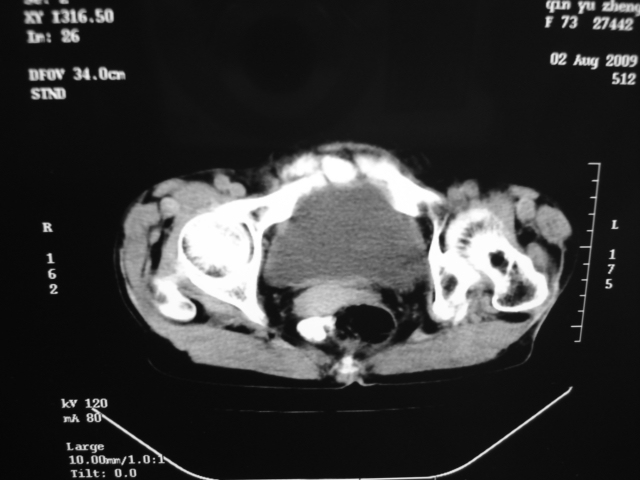

同事奶奶,73岁,腹痛一年,夜晚较重,潜血+++,拒绝增强,考虑左肾ca并腹膜后转移;请各位老师帮忙看看,谢谢!

左肾癌侵及输尿管上段,腹膜后多发淋巴结转移,脾脏钙化灶。至于潜血+++,要考虑消化道病变,本次ct片肠腔未见明显异常。

1)考虑左肾癌侵犯肾盂并腹膜后淋巴结转移。2)脾脏钙化灶。

考虑左肾癌侵犯肾盂并腹膜后淋巴结转移。